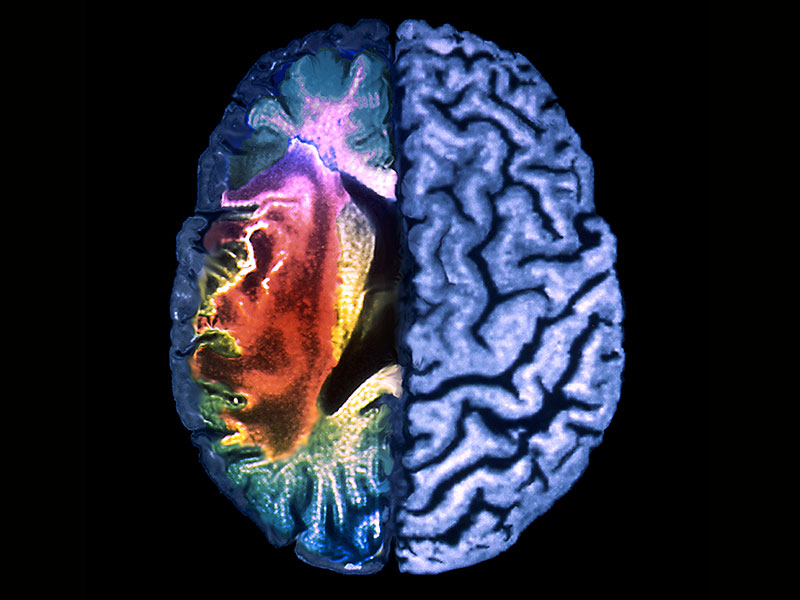

الشلل النصفي أو الجزئي أو شلل الأطراف الناتجه من الجلطات |

حالات ما بعد الجلطه الدماغيه والجلطه القلبيه |